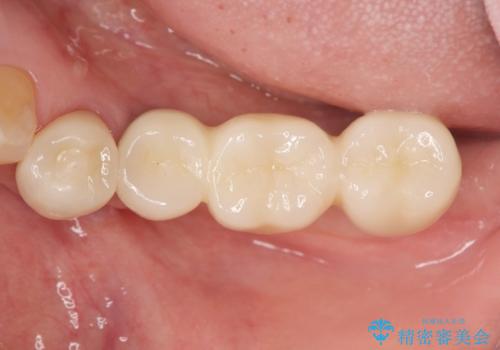

- 「奥歯がたくさん無くなってしまい、食事が楽しめるようにしっかりとかめるようにしてほしい。」という希望で来院されました。

入れ歯かインプラント治療の選択肢をご案内ししっかりと咀嚼機能を回復できる、インプラント治療を希望されました。

骨の量が比較的十分に保たれていたため、インプラントを埋入し1ヶ月後には仮歯を入れてしっかりと咬合機能を回復することができました。